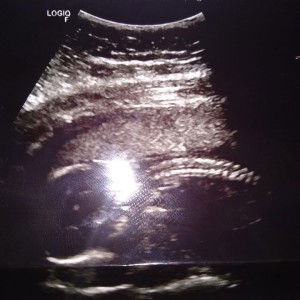

Meron po bang application n legit n nkakadetect kung anu gender ng mgging baby mo? ???